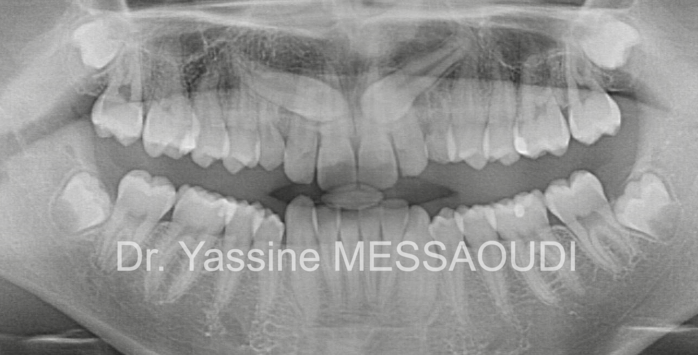

- scienceDents incluses et agénésies simples ou multiples

Traitement de canines incluses palatines bilatérales